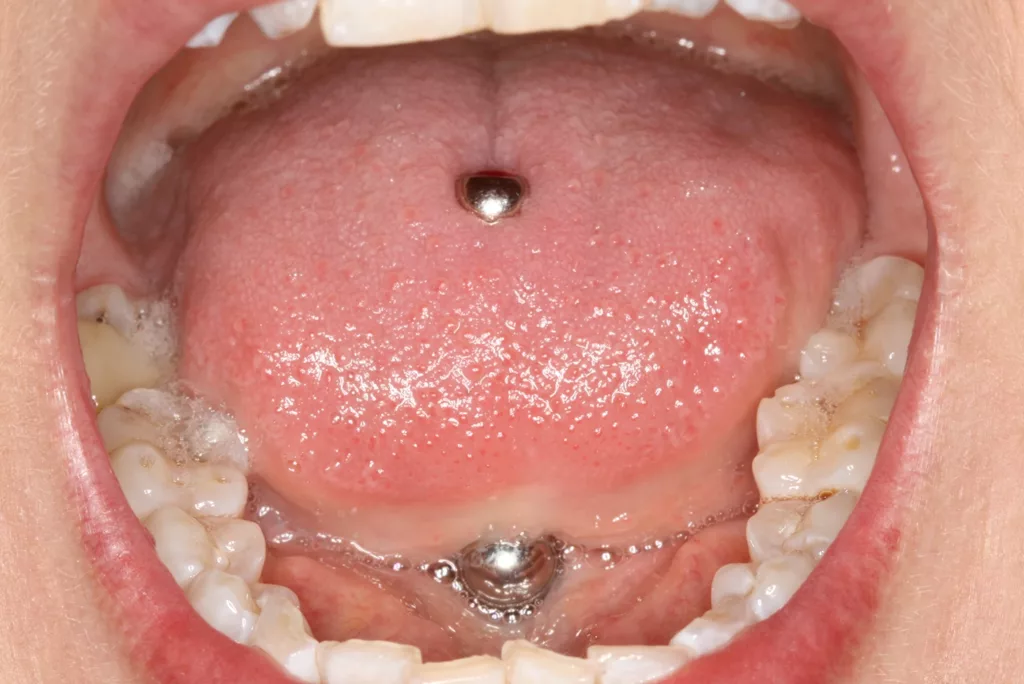

Im Kopfbereich befinden sich Piercings vornehmlich an den Ohren, aber auch an anderen Gesichtsregionen wie Nasenflügeln, Wangen oder Augenbrauen werden diese Accessoires getragen. Orale Piercings können sich an der Oberlippe, Unterlippe, Lippenfrenulum, Zunge, Zungenfrenulum und/oder der Uvula befinden [3]. Die Prävalenz oraler Piercings ist global variabel und schwankt je nach analysierter Bevölkerungsgruppe zwischen 3 und 20% [1]. Sie reicht in einigen Regionen sogar bis zu 50%. Andere Daten zeigen, dass die Prävalenz oraler und perioraler Piercings bei jungen Erwachsenen zwischen 0,8 und 12% liegt [2]. Der größte Teil entfällt dabei auf Zungen- und Lippenpiercings (Abb. 2a bis c).

Wir sind vor mittlerweile 17 Jahren erstmals mit der Frage etwaiger Auswirkungen oraler Piercings auf den Zahnhalteapparat konfrontiert worden [10]. Eine damals 24-jährige Patientin stellte sich mit einem ungewöhnlichen Befund vor (Abb. 3a bis d). Bei sonst parodontal unauffälligen Verhältnissen mit Sondierungstiefen zwischen 2 und 3 mm, reichten die Sondierungstiefen an den Schneidezähnen im Unterkiefer bis 12 mm. Zahn 41 schmerzte und wies eine erhöhte Lockerung von Grad 2 auf. Bukkal war zudem eine Fistel mit Pusentleerung zu detektieren. Die Patientin war allgemeinmedizinisch gesund, rauchte nicht und hatte auch keinen Diabetes mellitus. Eine familiäre Prädisposition für parodontale Erkrankungen ließ sich anamnestisch nicht konstruieren. Die Mundhygiene war zwar nicht perfekt, stand aber auch in keinem Verhältnis zu ihrem dramatischen lokalen parodontalen Befund. Im Rahmen der anamnestischen Befragung, fokussiert auf ungewöhnliche Habits, berichtete die Patientin, bis vor kurzem ein Zungenpiercing getragen zu haben, dieses aber vor ca. sechs Monaten entfernt zu haben. Die Piercing-Tragedauer betrug etwa drei Jahre.

![Abb. 3a: Klinische Dokumentation einer 24-jährigen Patientin mit einer weit fortgeschrittenen lokalen parodontalen Destruktion, die mit großer Wahrscheinlichkeit durch ein Zungenpiercing hervorgerufen wurde [10]. Mit Ausnahme der Symptomatik im Unterkiefer-Frontzahnbereich wies die Patientin flache Sondierungstiefen und einzelne Regionen mit Gingivitis auf. Die Zähne reagierten positiv auf eine Sensibilitätsprobe mit Kältespray. Das Piercing war zum Zeitpunkt der Vorstellung in der Klinik bereits nicht mehr im Mund. Es wurde eine stufenweise systematische parodontale Therapie eingeleitet. Die verbliebenen und nahezu unveränderten erhöhten Son¬dierungstiefen wurden einem parodontal-chirurgischen Eingriff mit zusätzlichen, die Regenera¬tion fördernden Maßnahmen (Straumann Emdogain, Straumann, Basel, Schweiz) unterzogen. Es wurde die für diese Operationen empfohlene Schnittführung im Sinne eines Papillenerhaltungs¬lappens angewendet. Der nach der Degranulierung mit Hand- und Ultraschallinstrumenten sicht¬bare knöcherne Defekt wies eine ungünstige Morphologie für die Regeneration auf. Ein primärer Wundverschluss wurde dennoch erzielt. Diese Ansätze blieben letztendlich erfolglos und der Zahn 41 ging verloren (parodontologische Therapie gemeinsam mit Dr. L. Büttel, Basel, Schweiz).](https://dentalwelt.spitta.de/wp-content/uploads/2025/07/Abb-3a-1024x684.webp)

![Abb. 3b: Klinische Dokumentation einer 24-jährigen Patientin mit einer weit fortgeschrittenen lokalen parodontalen Destruktion, die mit großer Wahrscheinlichkeit durch ein Zungenpiercing hervorgerufen wurde [10]. Mit Ausnahme der Symptomatik im Unterkiefer-Frontzahnbereich wies die Patientin flache Sondierungstiefen und einzelne Regionen mit Gingivitis auf. Die Zähne reagierten positiv auf eine Sensibilitätsprobe mit Kältespray. Das Piercing war zum Zeitpunkt der Vorstellung in der Klinik bereits nicht mehr im Mund. Es wurde eine stufenweise systematische parodontale Therapie eingeleitet. Die verbliebenen und nahezu unveränderten erhöhten Son¬dierungstiefen wurden einem parodontal-chirurgischen Eingriff mit zusätzlichen, die Regenera¬tion fördernden Maßnahmen (Straumann Emdogain, Straumann, Basel, Schweiz) unterzogen. Es wurde die für diese Operationen empfohlene Schnittführung im Sinne eines Papillenerhaltungs¬lappens angewendet. Der nach der Degranulierung mit Hand- und Ultraschallinstrumenten sicht¬bare knöcherne Defekt wies eine ungünstige Morphologie für die Regeneration auf. Ein primärer Wundverschluss wurde dennoch erzielt. Diese Ansätze blieben letztendlich erfolglos und der Zahn 41 ging verloren (parodontologische Therapie gemeinsam mit Dr. L. Büttel, Basel, Schweiz).](https://dentalwelt.spitta.de/wp-content/uploads/2025/07/Abb-3b-1024x684.webp)

![Abb. 3c: Klinische Dokumentation einer 24-jährigen Patientin mit einer weit fortgeschrittenen lokalen parodontalen Destruktion, die mit großer Wahrscheinlichkeit durch ein Zungenpiercing hervorgerufen wurde [10]. Mit Ausnahme der Symptomatik im Unterkiefer-Frontzahnbereich wies die Patientin flache Sondierungstiefen und einzelne Regionen mit Gingivitis auf. Die Zähne reagierten positiv auf eine Sensibilitätsprobe mit Kältespray. Das Piercing war zum Zeitpunkt der Vorstellung in der Klinik bereits nicht mehr im Mund. Es wurde eine stufenweise systematische parodontale Therapie eingeleitet. Die verbliebenen und nahezu unveränderten erhöhten Son¬dierungstiefen wurden einem parodontal-chirurgischen Eingriff mit zusätzlichen, die Regenera¬tion fördernden Maßnahmen (Straumann Emdogain, Straumann, Basel, Schweiz) unterzogen. Es wurde die für diese Operationen empfohlene Schnittführung im Sinne eines Papillenerhaltungs¬lappens angewendet. Der nach der Degranulierung mit Hand- und Ultraschallinstrumenten sicht¬bare knöcherne Defekt wies eine ungünstige Morphologie für die Regeneration auf. Ein primärer Wundverschluss wurde dennoch erzielt. Diese Ansätze blieben letztendlich erfolglos und der Zahn 41 ging verloren (parodontologische Therapie gemeinsam mit Dr. L. Büttel, Basel, Schweiz).](https://dentalwelt.spitta.de/wp-content/uploads/2025/07/Abb-3c-1024x722.webp)

![Abb. 3d: Klinische Dokumentation einer 24-jährigen Patientin mit einer weit fortgeschrittenen lokalen parodontalen Destruktion, die mit großer Wahrscheinlichkeit durch ein Zungenpiercing hervorgerufen wurde [10]. Mit Ausnahme der Symptomatik im Unterkiefer-Frontzahnbereich wies die Patientin flache Sondierungstiefen und einzelne Regionen mit Gingivitis auf. Die Zähne reagierten positiv auf eine Sensibilitätsprobe mit Kältespray. Das Piercing war zum Zeitpunkt der Vorstellung in der Klinik bereits nicht mehr im Mund. Es wurde eine stufenweise systematische parodontale Therapie eingeleitet. Die verbliebenen und nahezu unveränderten erhöhten Son¬dierungstiefen wurden einem parodontal-chirurgischen Eingriff mit zusätzlichen, die Regenera¬tion fördernden Maßnahmen (Straumann Emdogain, Straumann, Basel, Schweiz) unterzogen. Es wurde die für diese Operationen empfohlene Schnittführung im Sinne eines Papillenerhaltungs¬lappens angewendet. Der nach der Degranulierung mit Hand- und Ultraschallinstrumenten sicht¬bare knöcherne Defekt wies eine ungünstige Morphologie für die Regeneration auf. Ein primärer Wundverschluss wurde dennoch erzielt. Diese Ansätze blieben letztendlich erfolglos und der Zahn 41 ging verloren (parodontologische Therapie gemeinsam mit Dr. L. Büttel, Basel, Schweiz).](https://dentalwelt.spitta.de/wp-content/uploads/2025/07/Abb-3d-1024x665.webp)